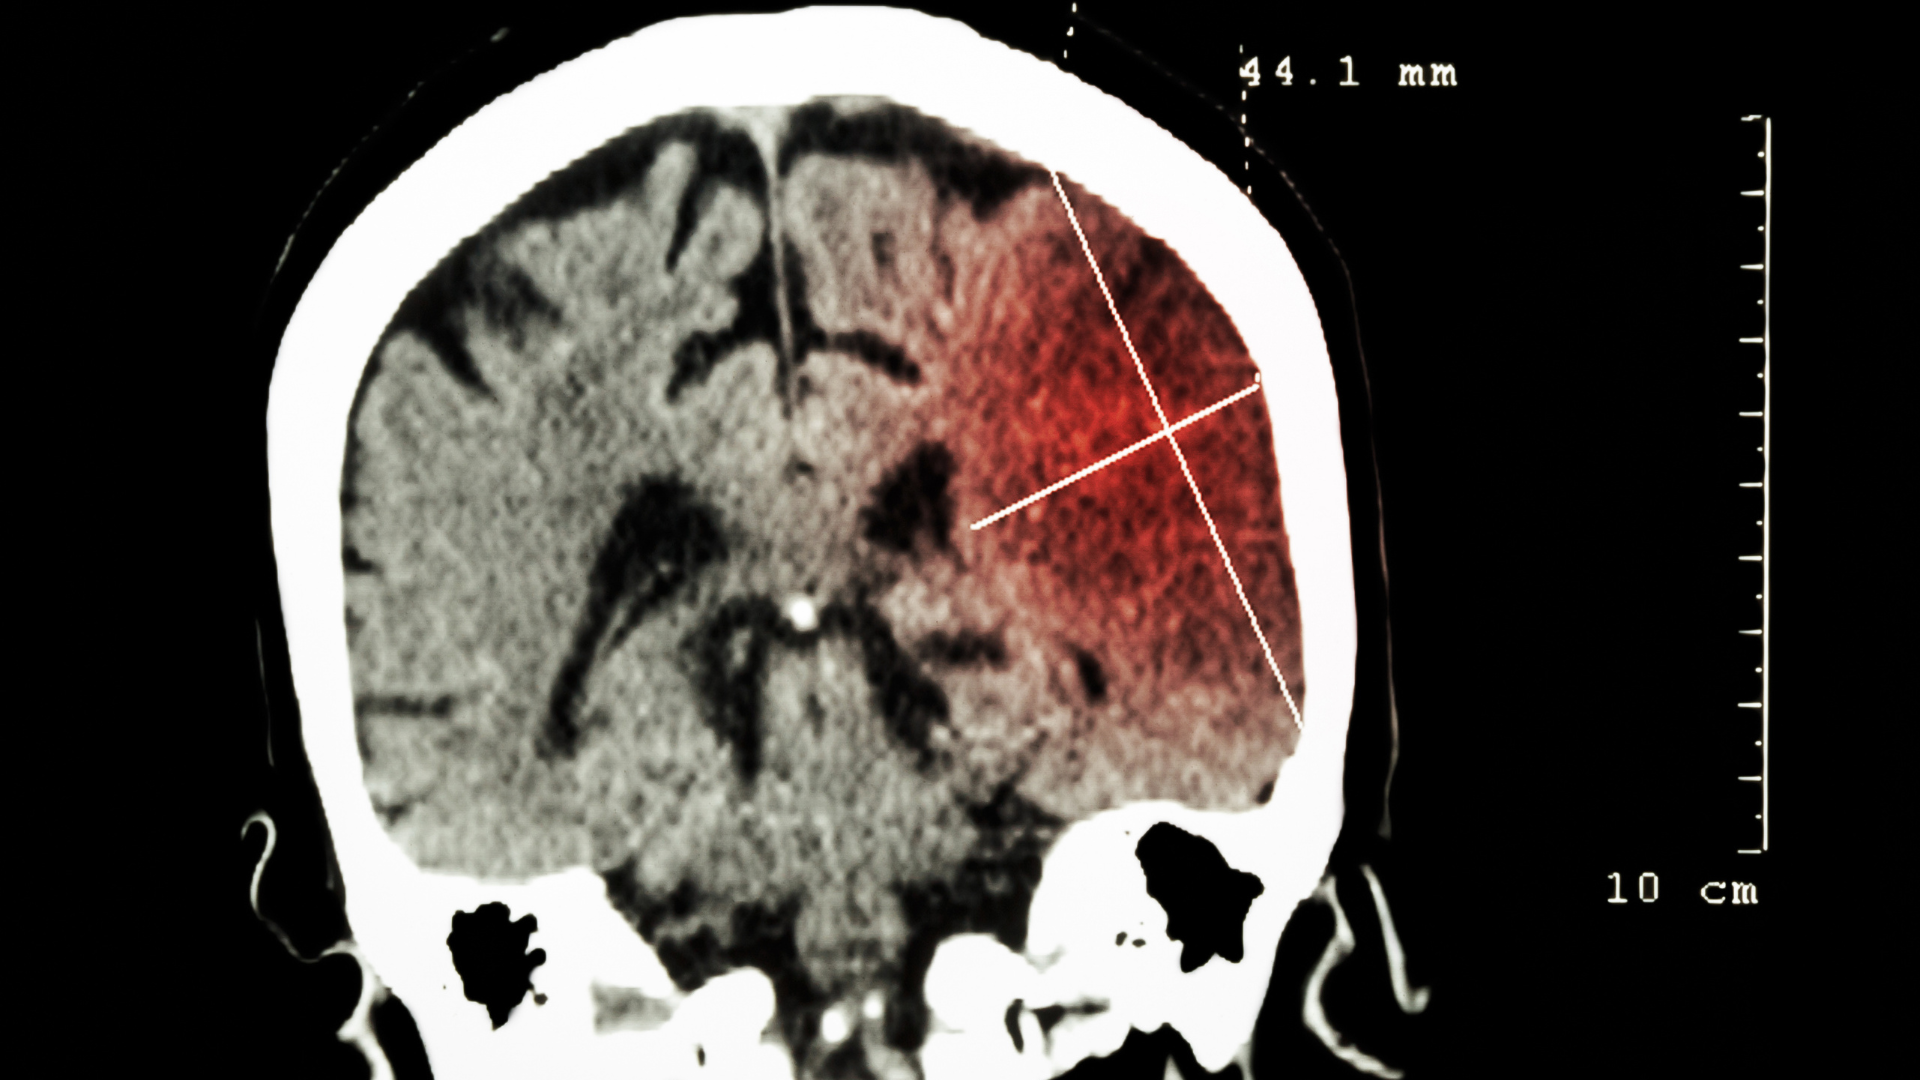

- Thiếu máu não và tổn thương mạch máu như đột quỵ nhồi máu não hoặc xuất huyết não, thiếu máu não mạn tính.

- Chẩn đoán hình ảnh như MRI/CT scan để phát hiện u não, đột quỵ, xuất huyết, PET scan giúp đánh giá lắng đọng protein bất thường.